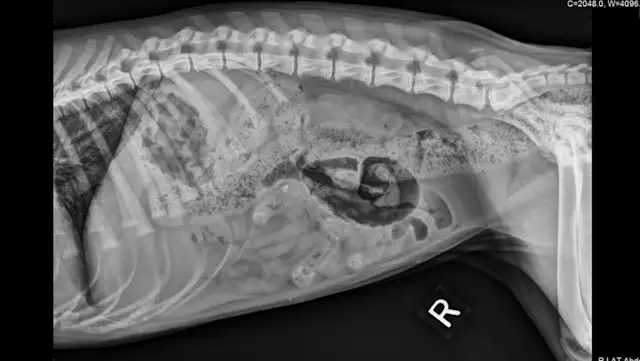

FIGURE 1: Lateral Abdominal View

The lateral abdominal view includes the entire diaphragm cranially and the greater trochanter caudally. Position the cranial edge of the collimator light 2 to 3 fingerbreadths cranial to the xiphoid process. Align the caudal edge of the light at the level of the greater trochanter. Center the beam over the caudal aspect of the 13th rib.1 Using soft ropes or tape, pull the thoracic limbs cranially and pelvic limbs caudally. Pulling the hind limbs caudally will help eliminate superimposition of the femoral muscles over the caudal portion of the abdomen.1  Collimate to include the patient’s dorsal and ventral borders in the radiograph.